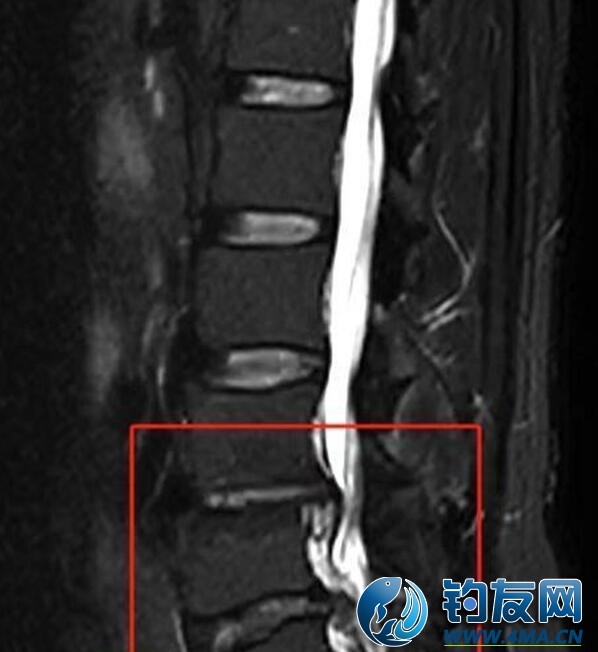

入院后,急診科醫生迅速為余先生完善了一系列相關檢查。核磁共振結果顯示余先生存在一系列腰椎問題,最終他被診斷為腰椎椎管狹窄、腰椎間盤脫出伴坐骨神經痛以及脊周圍神經損傷,隨后,余先生被轉入武漢市普仁醫院脊柱骨科進行后續針對性治療。

核磁共振可見患者椎間盤脫出、椎管狹窄、脊髓神經嚴重受壓

“患者的腰椎狀況頗為復雜,其中尤以椎間盤脫出、椎管狹窄導致脊髓神經受壓這一狀況最為嚴重,除此之外,還存在骨質增生、終板炎、椎間盤變性等多種異常表現。因為腰椎椎管狹窄以及椎間盤脫出等問題,已經導致了馬尾神經受壓,影響下肢的感覺、運動功能,如果不及時通過手術解除這種壓迫,神經功能可能會進一步受損,甚至出現不可逆的傷害,嚴重影響患者日后的生活質量,最終導致大小便失禁、下肢永久性癱瘓等嚴重后果。面對如此棘手的病情,為了避免出現更糟糕的情況,患者需盡快進行手術治療。”武漢市普仁醫院脊柱骨科主治醫師余雙奇解釋道。